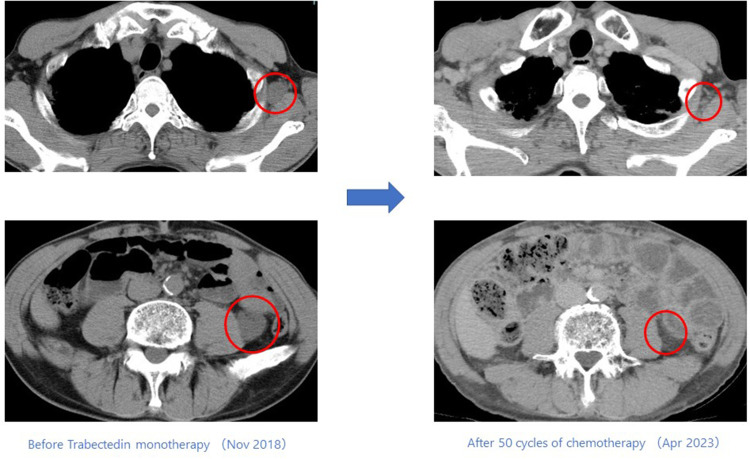

Case presentation: Case 1: A 44-year-old male started trabectedin as second-line therapy after initial chemotherapy, which included doxorubicin. To date, he has completed 9 cycles, showing a response for 6 months. Case 2: A 71-year-old male, deemed intolerant to doxorubicin, started trabectedin as his first-line treatment. He has undergone 50 cycles to date, maintaining a response for 56 months. Case 3: A 59-year-old female began trabectedin as second-line therapy after initial chemotherapy, including doxorubicin. She responded for 6 months before experiencing disease progression. Case 4: A 79-year-old male developed new lesions after one course of initial chemotherapy, including doxorubicin. He then began trabectedin and has maintained a response for 10 months to date.

背景:肌样脂肪肉瘤是一种罕见的肿瘤类型,约占所有脂肪肉瘤的30%。在基础研究和一些临床实验中,携带 FUS/CHOP 融合基因的类粘液性脂肪肉瘤使用曲贝替定取得了良好的效果。然而,曲贝替定对未接受化疗的软组织肉瘤或FUS/CHOP融合基因阳性的肌样脂肪肉瘤的有效性和安全性尚未确定。因此,我们评估了本院四例携带FUS/CHOP融合基因的类粘液性脂肪肉瘤患者接受曲贝替定单药治疗的有效性和安全性:我们分析了在冈山大学接受手术并在川崎医学院接受化疗的四例转移性肌样脂肪肉瘤患者。这些患者的 FUS/CHOP 融合基因检测结果呈阳性,通过 RT-PCR 技术辅助病理诊断。从冷冻肿瘤标本的肿瘤组织切片中提取 RNA。反转录后,使用 TLS/FUS-CHOP 引物进行 PCR。对得到的产物进行电泳,然后确认核苷酸序列:病例 1:一名 44 岁的男性患者在接受了包括多柔比星在内的初始化疗后,开始接受曲贝替定作为二线疗法。迄今为止,他已完成了 9 个周期的化疗,并在 6 个月内出现了反应。病例 2:一名 71 岁的男性患者被认为不能耐受多柔比星,他开始接受曲贝替定作为一线治疗。迄今为止,他已接受了 50 个周期的治疗,56 个月来一直保持着应答。病例 3:一名 59 岁的女性患者在接受了包括多柔比星在内的初始化疗后,开始将曲贝特林作为二线疗法。她在治疗 6 个月后病情出现进展。病例 4:一名 79 岁的男性患者在接受了包括多柔比星在内的一个疗程的初始化疗后出现了新的病变。随后,他开始接受曲贝替定治疗,迄今已有10个月的应答:结论:与其他化疗方法相比,曲贝替丁(Trabectedin)对携带FUS/CHOP融合基因的肌样脂肪肉瘤患者具有潜在的更高疗效和良好的安全性。